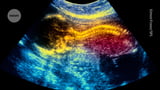

A first-in-human CuRE trial tested placenta-derived mesenchymal stem cells seeded onto an FDA-approved extracellular matrix and applied to the exposed spinal cord during standard open fetal surgery for myelomeningocele, a severe form of spina bifida.

MRI after birth showed reversal of hindbrain herniation in all treated infants, and no tumor formation or tissue abnormalities were observed at birth.

The stem-cell patch was embedded in a matrix and applied to the exposed spinal cord alongside standard fetal repair, aiming to promote spinal tissue growth and address neural damage beyond surgery alone.